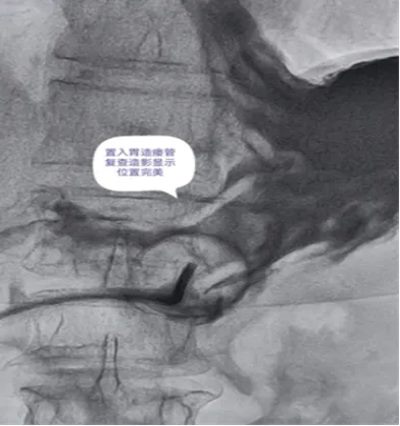

DSA引导下经皮胃造瘘术,是在数字减影血管造影(DSA)这个“透视眼”的实时可视化导航下,于患者腹壁上建立一个仅 3-5毫米 的微小穿刺点。通过这个“针眼”,医生精准地将一根营养管直接置入胃部,建立起一条直达的营养通道。

整个过程就像一次精准的“导航穿刺”,全程操作便捷、创伤小,却能完美替代传统的鼻饲管,为患者提供长期、稳定、安全的营养支持。

DSA影像全程清晰可视化,可精准避开血管、脏器等重要组织,穿刺定位误差小;穿刺创口仅3-5mm,出血量少,术后反流、误吸、肺炎等并发症发生率低于5%,术后1-2天即可正常喂养,恢复速度快。

医院临床实践中就有典型案例:一名65岁食道癌伴淋巴结转移患者,因食道狭窄无法插入胃镜,且体质虚弱难以耐受全麻手术,团队借助DSA精准导航,仅用10分钟便完成手术,局部麻醉下患者全程无明显不适,术后1天即可通过造瘘管补充营养,为后续抗肿瘤治疗顺利开展奠定了坚实基础。